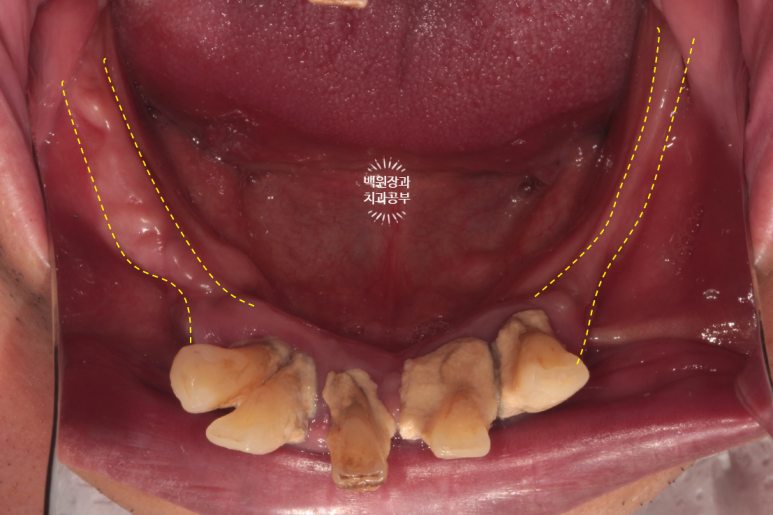

혹시나 보이시나 모르겠지만, 상당히 잇몸뼈가 얇음이.. 예상되는 상태였습니다.

노란색으로 잇몸뼈의 두께를 대략적으로 표시해두었는데요, 이미 치아들은 모두 사라져 있었지만 시간이 지나서도 엄청난 만성 치주염이 있었으리라는 것을 짐작해볼 수 있었습니다..